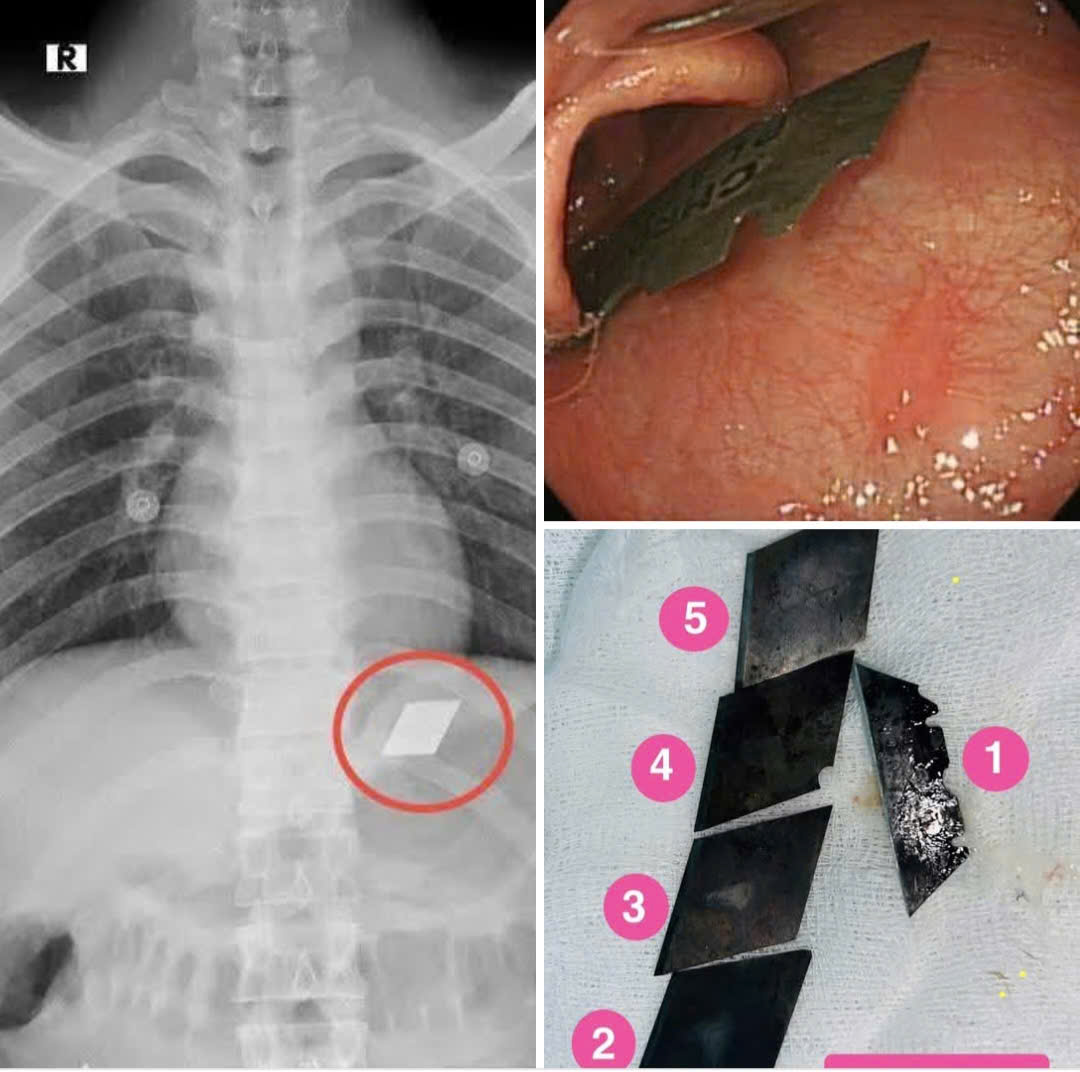

5 mảnh dao được gắp ra khỏi bụng một nạn nhân "ngáo đá"

Bác sĩ Quốc Du, người trực tiếp thực hiện ca phẩu thuật đã lấy một nửa cây dao lam kẹt ở miệng thực quản, hạ họng và 4 mảnh dao rọc giấy trong dạ dày

Sau can thiệp nội soi gắp các mảnh dao ra ngoài, bệnh nhân được cho nhập viện theo dõi. Hiện tại đã ổn định và xuất viện.